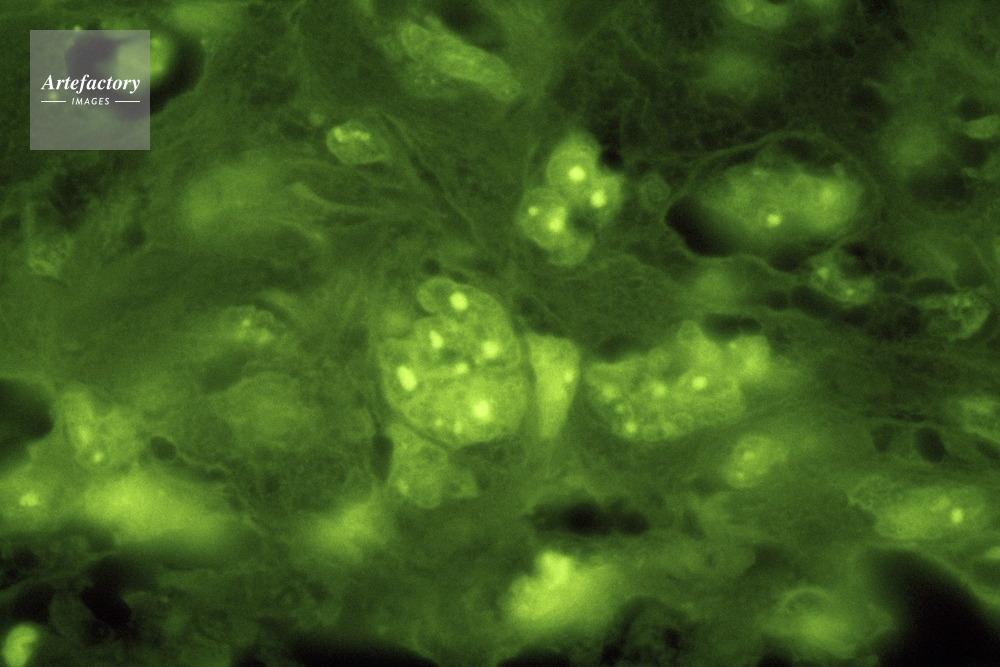

| 作品タイトル | ヒト唾液腺扁平上皮癌 | モデルリリース | なし | |

| キャプション | 蛍光NORs | 制限事項 | ||